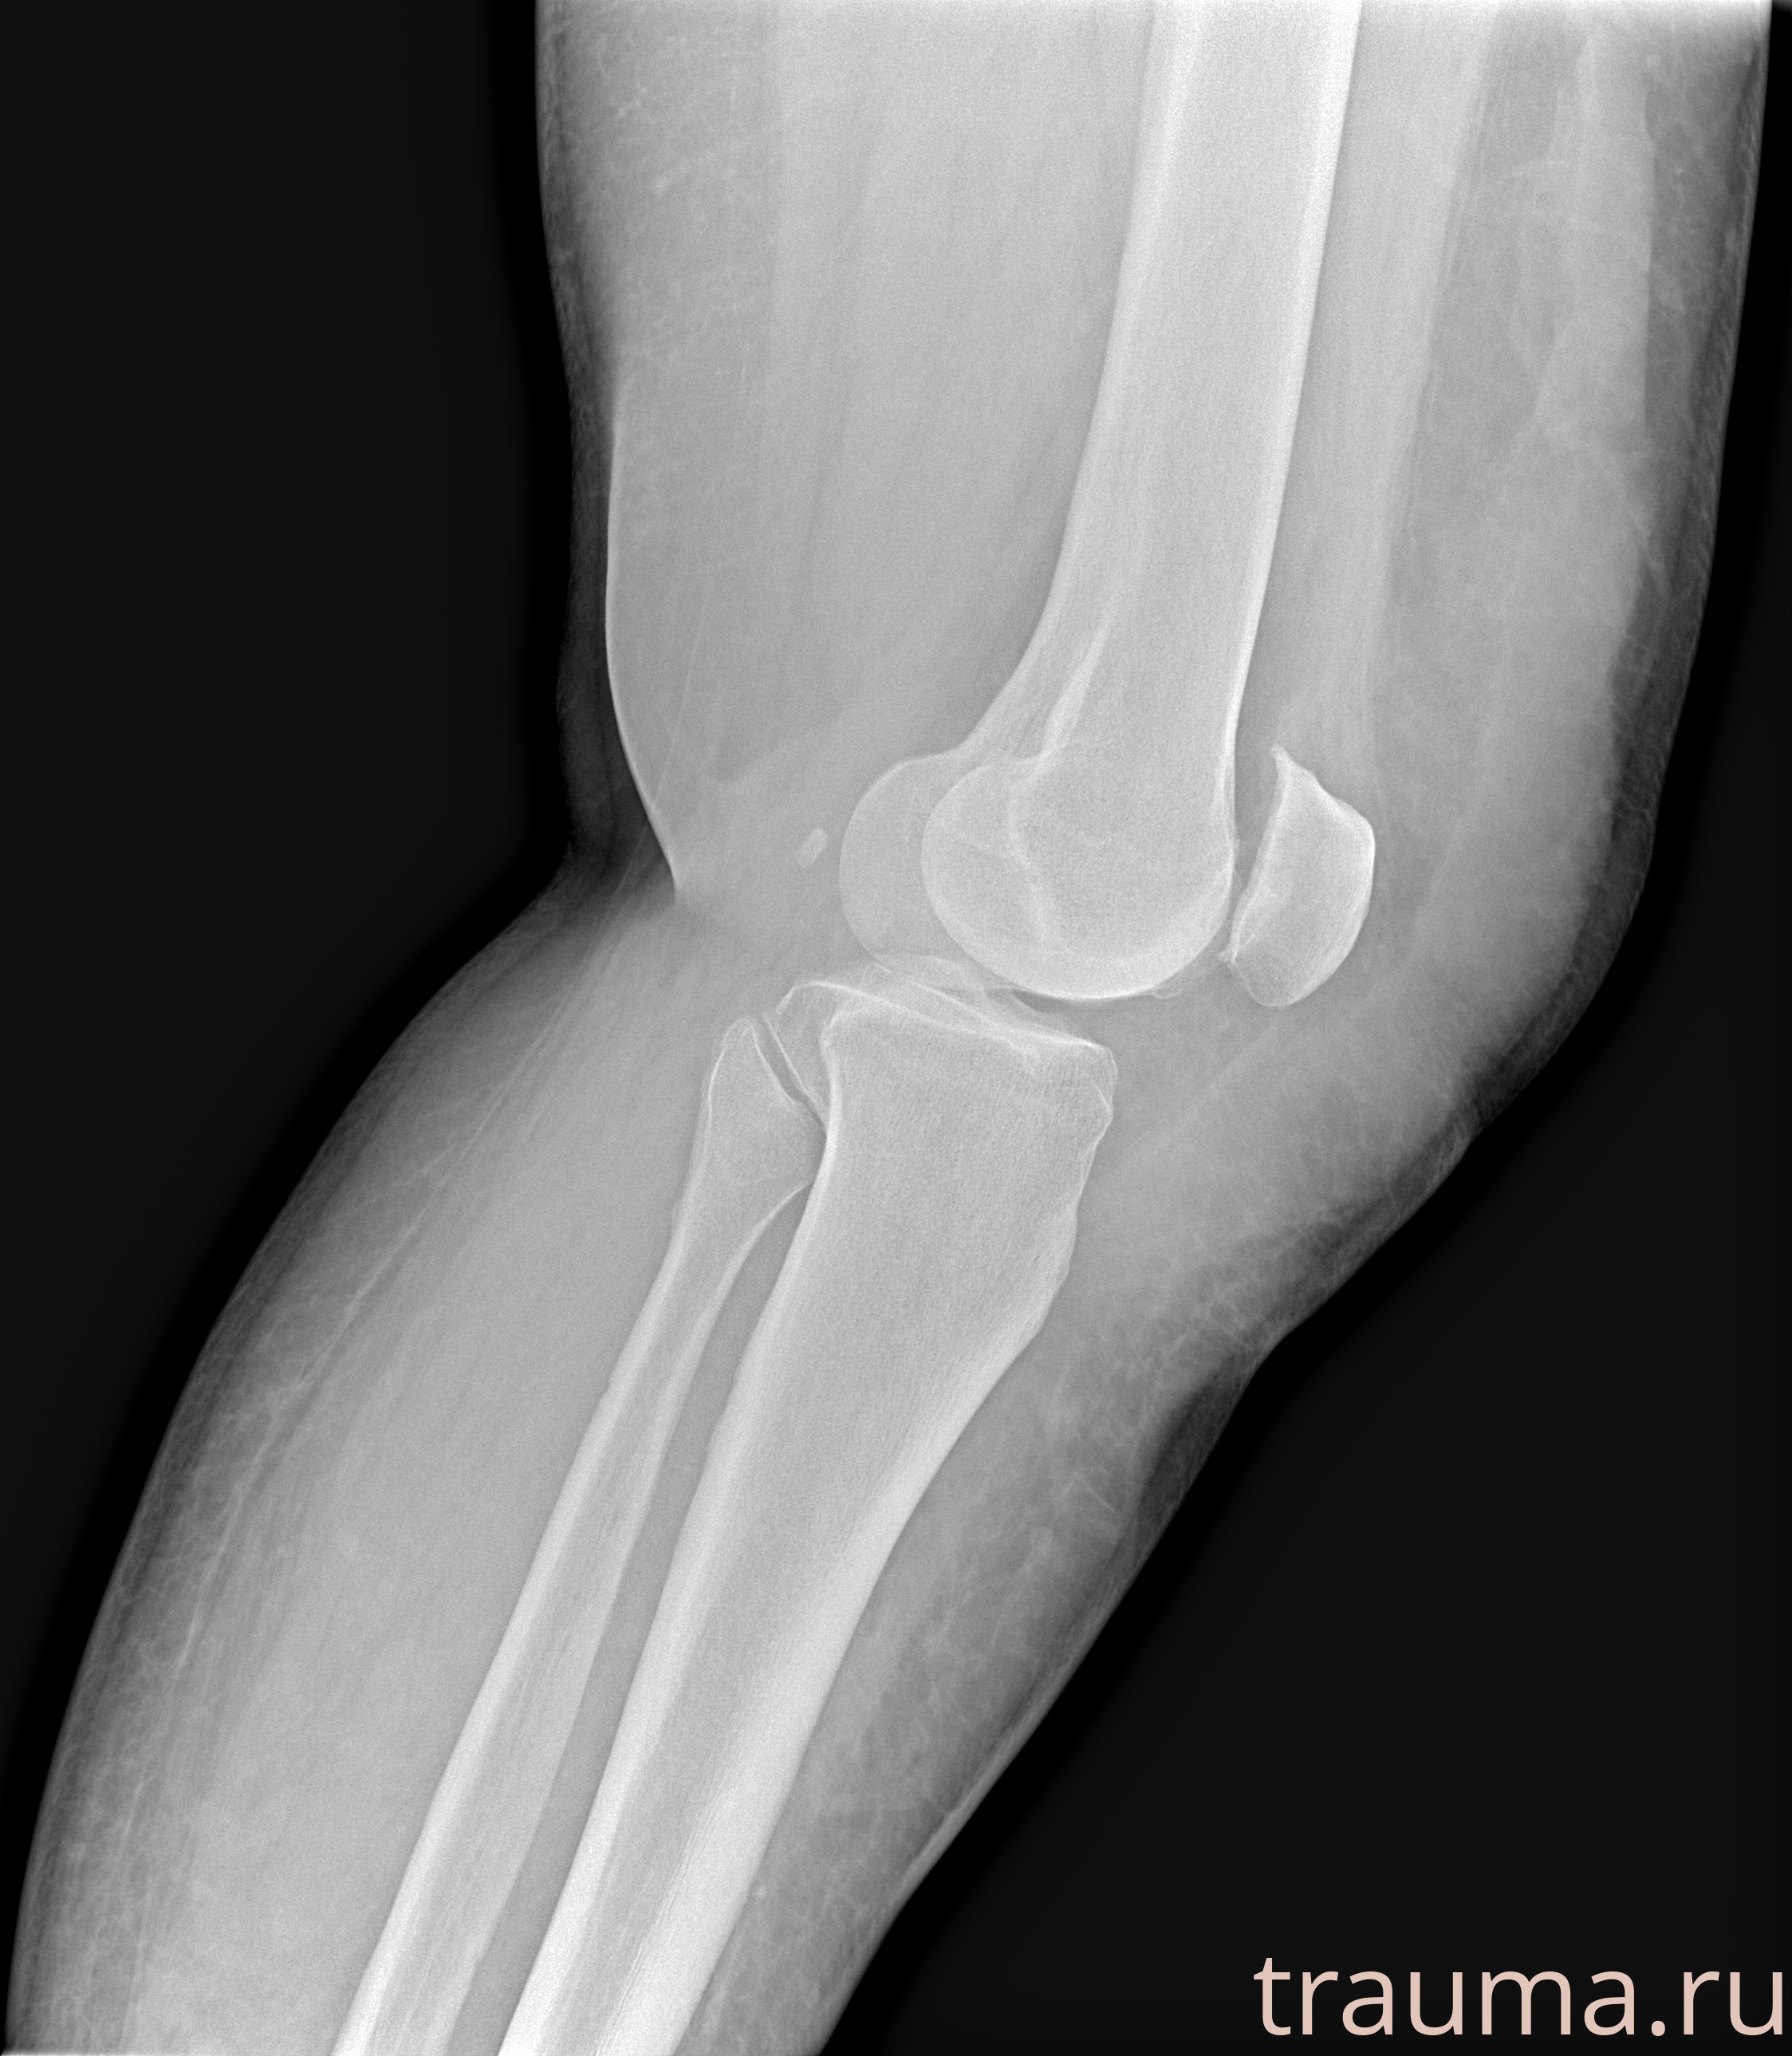

Рентгенограммы

Рентген на дому: по вашему адресу приезжает врач-рентгенолог, травматолог-ортопед с мобильным рентгеновским аппаратом, проводит диагностику травмы или заболевания, делает необходимые рентгенограммы, дает рекомендации по дальнейшему лечению. Получить качественные снимки в домашних условиях возможно благодаря уникальной методике, разработанной МосРентген Центром для института  Склифосовского